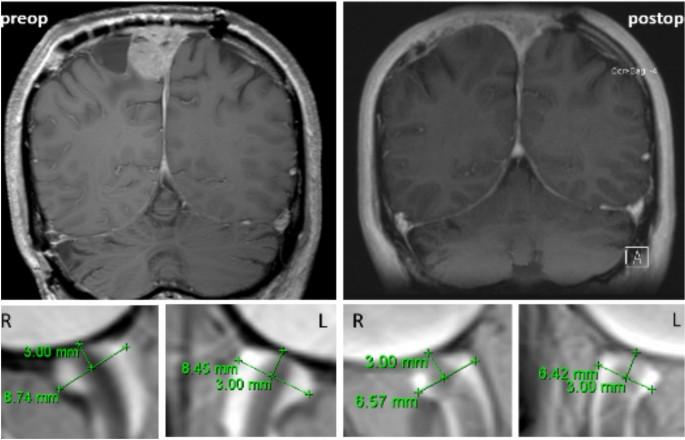

figure 1